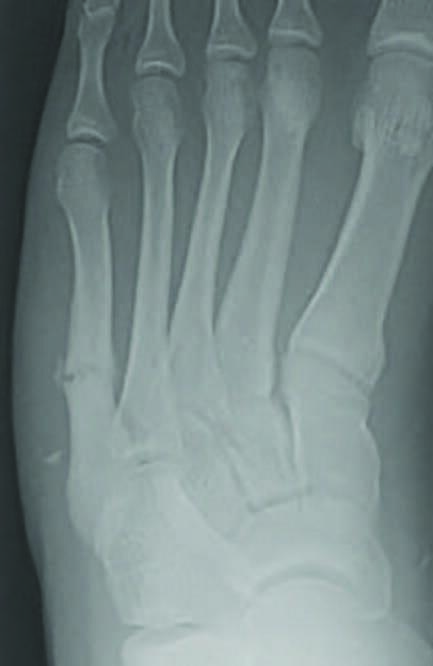

Fifth metatarsal fractures have been classified by Lawrence and Dameron based on the location of the fracture.1 Zone 1 fractures include the proximal tuberosity of the fifth metatarsal, referred to as avulsion fractures or pseudo-Jones fractures (see first photo above).

Zone 2 fractures are Jones fractures, located 1.5 cm proximal to the tuberosity, extending into the fourth and fifth intermetatarsal joint (see second photo above). This fracture is more severe due to tenuous blood supply at the metaphyseal-diaphyseal junction.4-6 Smith and team studied 10 fresh frozen cadaver specimens following arterial injection of India ink or barium sulfate, and reported that metatarsal blood supply arises from the nutrient artery, metaphyseal perforators, and periosteal arteries. They noted a watershed area between the nutrient artery and the metaphyseal perforators, corresponding to an area of poor healing as the nutrient artery terminates at the proximal diaphysis and metaphyseal vessels supply the tuberosity.1,5 Dameron reported a non-union rate of 25 percent in this fracture pattern.7

Lawrence and Dameron Zone 3 fractures are typically considered stress fractures and occur in the proximal diaphysis of the distal to the fourth and fifth intermetatarsal joint (see third photo above).

As previously mentioned, fifth metatarsal fractures may be due to acute trauma or repetitive stress. Avulsion fractures of the fifth metatarsal base, at Zone 1, are due to acute forefoot supination with plantarflexion, resulting in pull from the lateral band of the plantar fascia, abductor digiti quinti minimi, and/or peroneus brevis causing a transverse to slightly oblique fracture pattern.1 Avulsion fractures are more common in recreational and non-competitive athletes.3 Zone 2, Jones fractures, result from adduction force to the forefoot with the ankle plantarflexed. Zone 3, diaphyseal fractures, are most commonly due to stress1 and forced dorsiflexion of a plantarflexed and inverted forefoot, leading to a spiral/ oblique fracture pattern.7 Fifth metatarsal shaft and distal diaphyseal fractures are referred to as dancer’s fractures, common in ballet dancers rolling over their foot with the ankle in plantarflexion while applying both torsional force and axial loading to the metatarsal, leading to a long spiral diaphyseal fracture.3,9